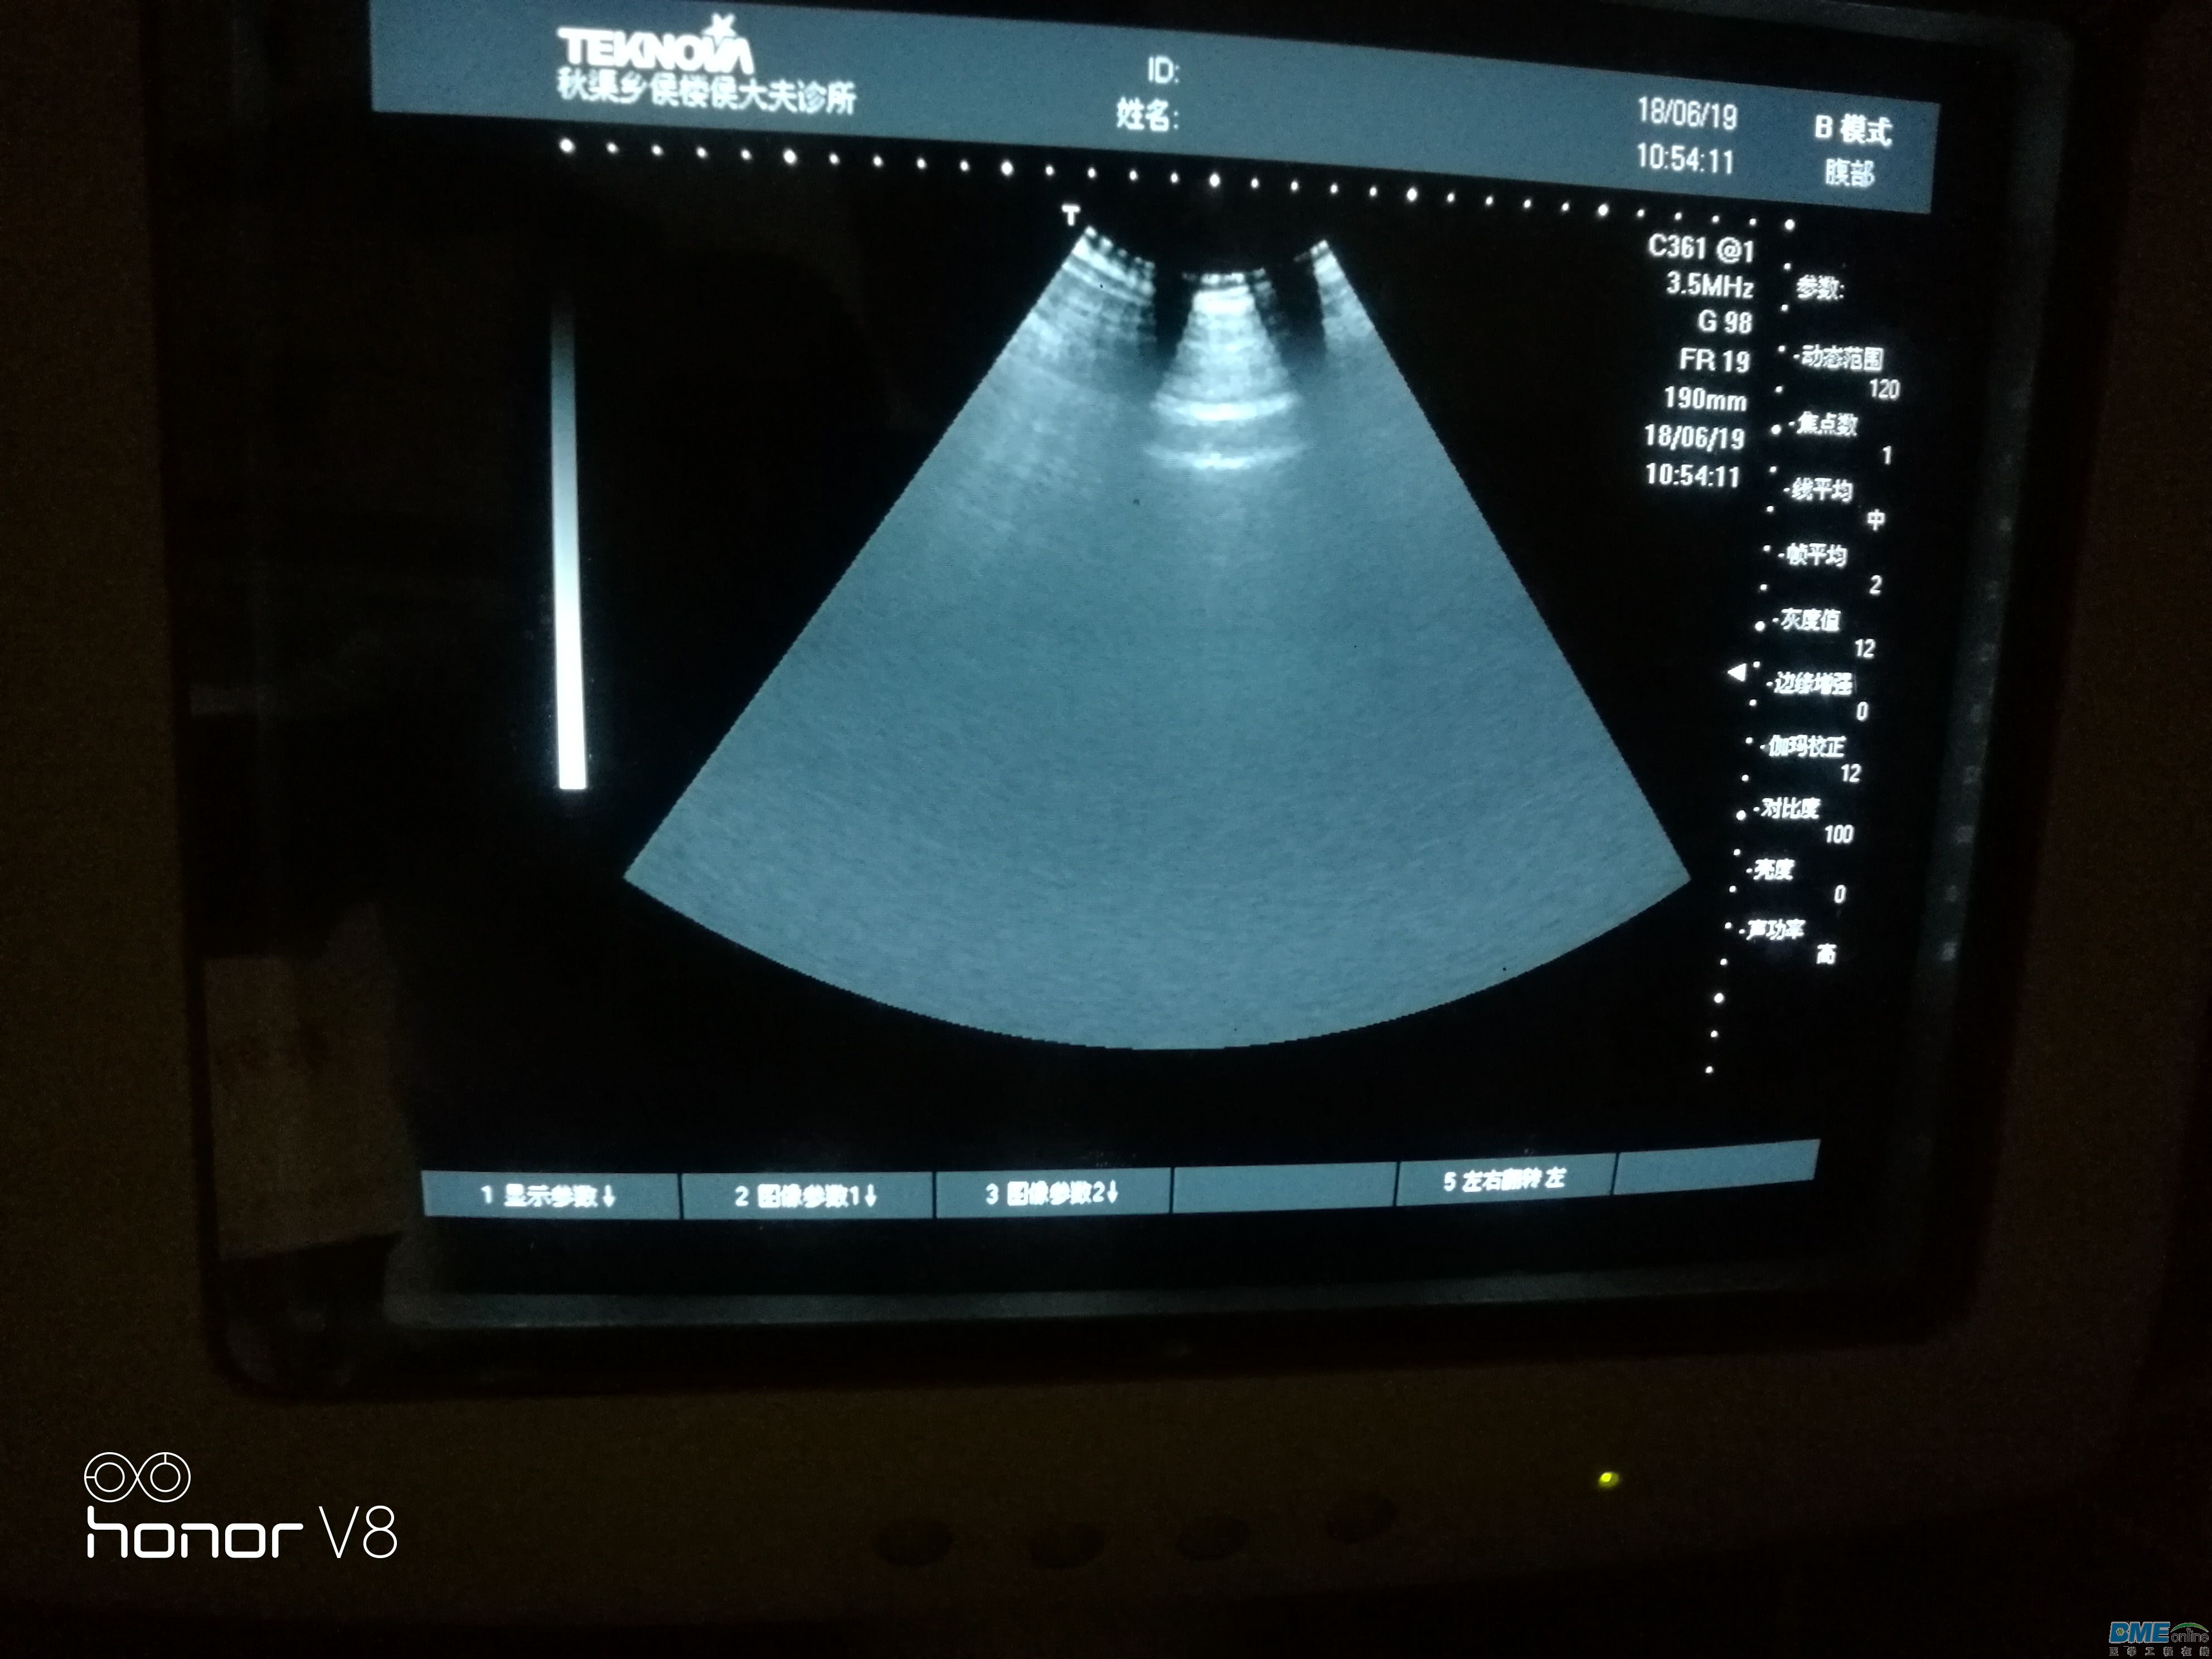

今天接收一台天惠华TH-200的B超级,问题是扇形区域里图像变小,如图扇形区域里只有上部分有图像,拔下探头图像不变。

,下面图是接入探头后直接测试腹部的图片,图上可以看出隐隐约约的影像探头接入后探测腹部扇形区域能有阴影的影像,开机拔去探头扇形区域只有一点点影像!求教维修思路